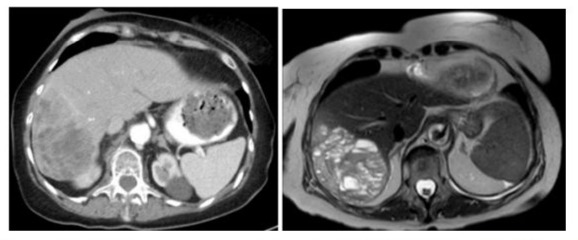

Case

Figure 1: A. CT scan showing a large heterogeneously enhancing mass of the right hepatic lobe B. MRI of multiloculated cystic mass in the posterior segment of the right hepatic lobe measuring approximately 11.4 x 7.8 x 8.6 cm.